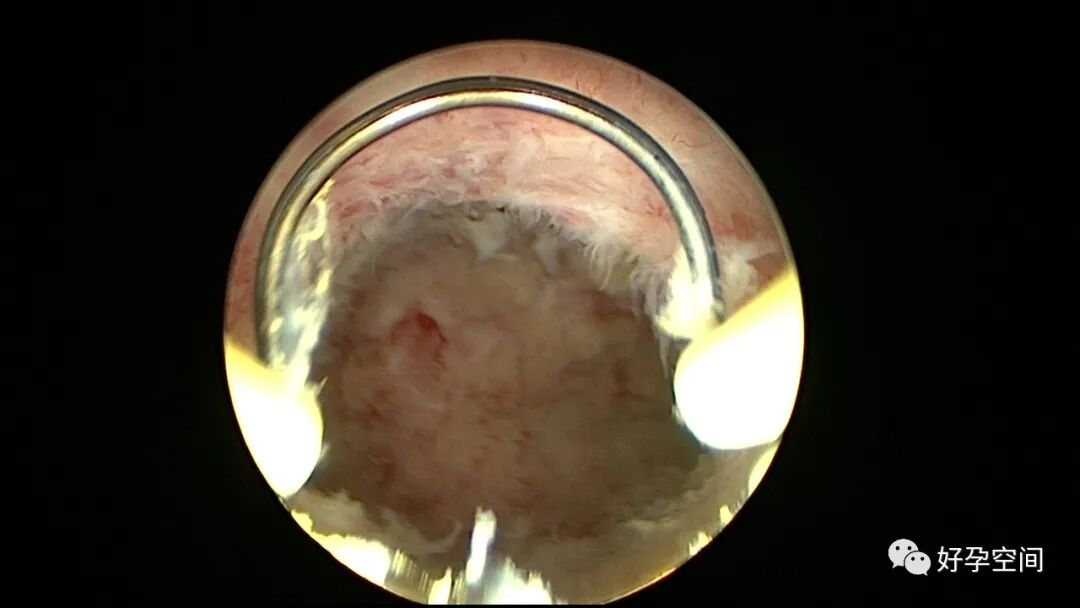

子宫内膜结核是由结核分枝杆菌在子宫内膜部位种植引起的炎症,是仅次于输卵管结核的常见女性生殖器结核。子宫内膜结核常由输卵管结核蔓延而来,多继发于盆腔腹膜结核或肺结核。子宫内膜结核的超声表现主要为:子宫内膜回声不均匀、宫腔内结节样病灶、宫腔内强回声灶、单纯的子宫内膜薄等。盆腹腔超声显示输卵管炎性表现:输卵管增粗、肥厚、扭曲、僵硬、输卵管积液积脓、卵巢旁混合性包块、输卵管系膜囊肿、盆腔包裹性积液等。术中所见:盆腹腔组织粘连、盆腹腔粟粒样结节、结核球、脓肿等,输卵管伞端烟斗样外翻,输卵管内充满淡黄色干酪样或豆渣样组织。宫腔镜显示宫腔狭窄、宫壁僵硬、宫内膜肉芽肿样增生、内膜质脆易刮除、干酪样组织、脓液等。

温宝宁等将子宫内膜结核宫腔镜检查的镜下表现分为:①宫腔形态、大小正常,双侧输卵管开口可见,子宫内膜发红、增厚,局部突起,表面可见少量质脆的小颗粒状赘生物,可刮出质脆的子宫内膜组织;②宫腔形态正常,但是宫腔内无正常子宫内膜,均被覆一层苍白的绒毛状或棉絮状质脆组织,血管少,无异形血管,宫腔内病灶与正常组织分界明显;③宫腔形态异常,呈窄桶状,子宫内膜瘢痕化,输卵管开口细小,甚至宫角消失。